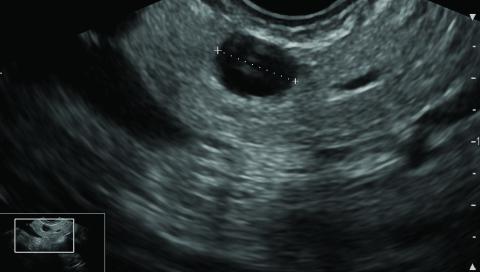

Endoscopic ultrasound showing a suspected 7-mm branch duct intraductal papillary mucinous neoplasm of the pancreas.